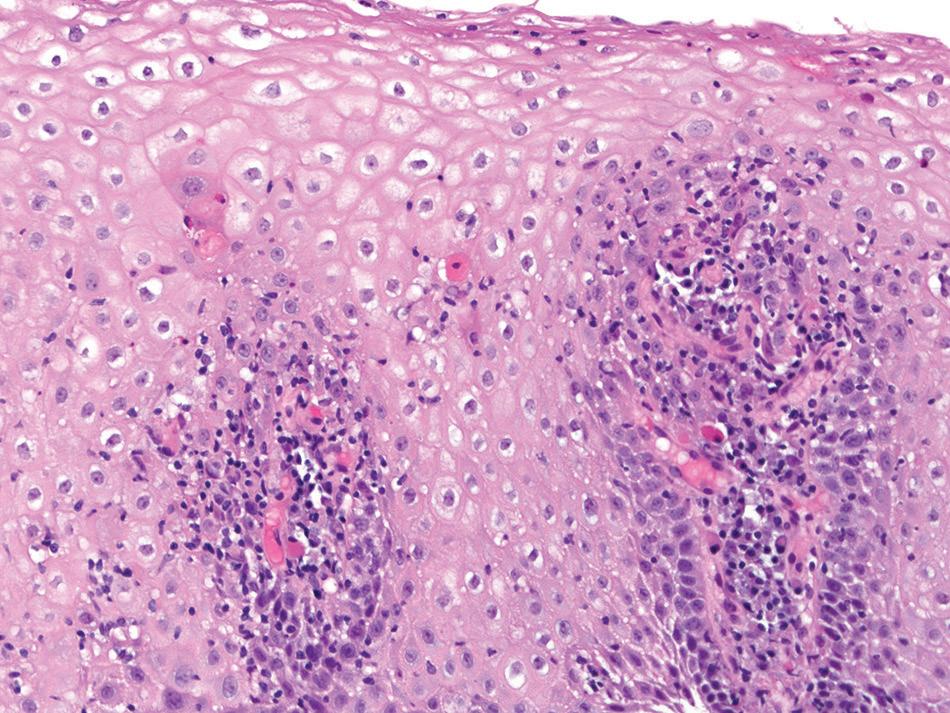

Histologic findings are usually localized to the lower esophagus and taper off or are virtually absent in the proximal segment of esophagus. The typical histologic features include basal cell hyperplasia (thickening of the basal layer to >15% of the total epithelial thickness or more than four to six basal cell layers in well-oriented sections), elongation of the papillae (>60% of the total epithelial thickness), and spongiosis (Fig. 1.2). Inflammatory changes include increased numbers of lymphocytes (Fig. 1.3), neutrophils, and eosinophils (Fig. 1.4). Erosions or ulcers are typically associated with severe GERD. Intraepithelial lymphocytes are predominantly T cells, which tend to acquire an elongated shape (“squiggly lymphocytes”) while traversing between the intercellular spaces. Additional findings including balloon cell change (Fig. 1.5) and hyperkeratosis.

reflux esophagitis. Basal cell hyperplasia, elongation of papillae, and spongiosis.

reflux esophagitis. increased numbers of intraepithelial lymphocytes are present among dilated intercellular spaces (spongiosis).